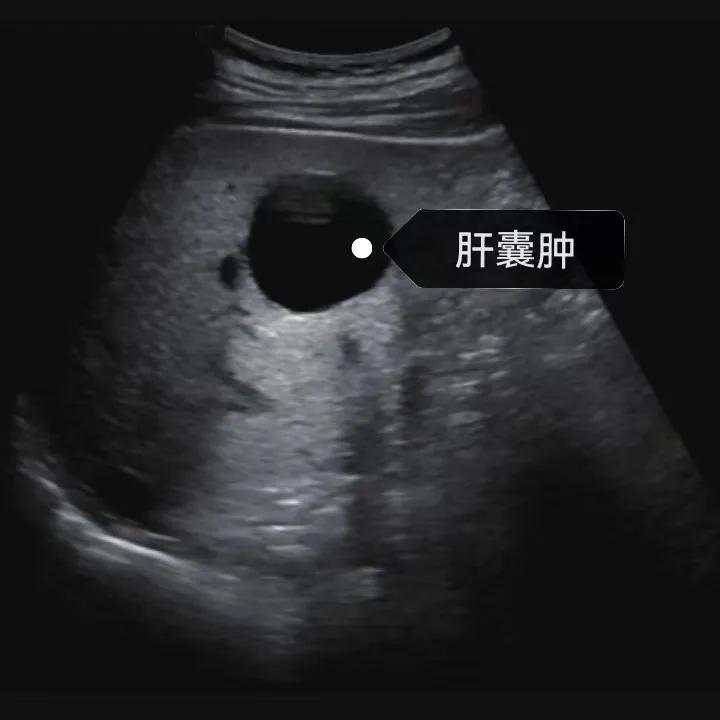

肝囊腫是一種常見的肝臟良性疾病,呈圓形或橢圓形,外由上皮細胞包裹形成包膜,內(nèi)由清亮、無色、無細胞成分的囊液填充,看上去就像是一顆注滿了水的氣球,因此通俗一點說就是肝臟中的“水泡”。

超聲通常是診斷肝囊腫的首選方法,彩超對肝囊腫的檢出率可達98%,<1cm的囊腫也可檢出。肝囊腫常表現(xiàn)為圓形或橢圓形無回聲,包膜光滑完整,邊界清晰,可有側(cè)壁回聲失落征象,后方回聲增強。病程長、囊腫較大者或囊內(nèi)有過出血、感染者,無回聲腔內(nèi)可見少量絮狀回聲漂浮。超聲對肝囊腫的診斷準確而靈敏,且方法簡單、無創(chuàng)、費用低、可重復性高,因此常常被作為首選。